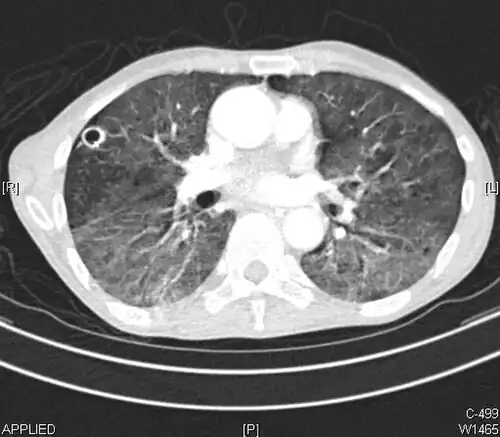

High-resolution CT image showing ground-glass opacities in the periphery of both lungs in a patient with COVID-19 (red arrows). The adjacent normal lung tissue with lower attenuation appears as darker areas.

CT image in patient with COVID-19 showing bilateral ground-glass opacities at the periphery of both lungs.

Ground-glass opacity is among the most common imaging findings in patients with confirmed COVID-19.[16][17] One systematic review found that among patients with COVID-19 and abnormal lung findings on CT, greater than 80% had GGOs, with greater than 50% having mixed GGOs and consolidation.[16] GGOs with mixed consolidation has most often been found in elderly populations.[18] Several studies have described a pattern among initial, intermediate, and hospital discharge imaging findings in the disease course of COVID-19. Most commonly, initial CT imaging reveals bilateral GGOs at the periphery of the lungs. During initial stages, this is most often found in the lower lobes, although involvement of the upper lobes and right middle lobe has also been reported early in the disease course.[16][18] This is in contrast to the two similar coronaviruses, SARS and MERS, which more commonly involve only one lung on initial imaging.[19][20] As the COVID-19 infection progresses, GGOs typically become more diffuse and often progress to consolidation.[11][18] This is sometimes accompanied by the development of a crazy paving pattern and interlobular septal thickening.[18] In many cases the most severe pulmonary CT abnormalities occurred within 2 weeks after symptoms began.[17] At this point, many individuals begin showing resolution of consolidation and GGOs as symptoms improve. However, some patients have worsening symptoms and imaging findings, with further increase in septal thickening, GGOs, and consolidation. These patients may develop lung "white-out" with progression to acute respiratory distress syndrome (ARDS) requiring treatment escalation.[17][21]